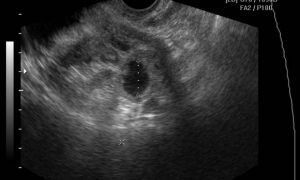

- Трансвагинальное узи- очень ценный диагностический инструмент,который позволяет увидеть изменения при остром аднексите и тубоовариальном образовании. При помощи узи можно дифференцировать боль при эндометриозе, эндометрите, остром аппендиците, разрыве кисты яичника, почечной колике и при многих других заболеваниях, сопровождающихся болью внизу живота